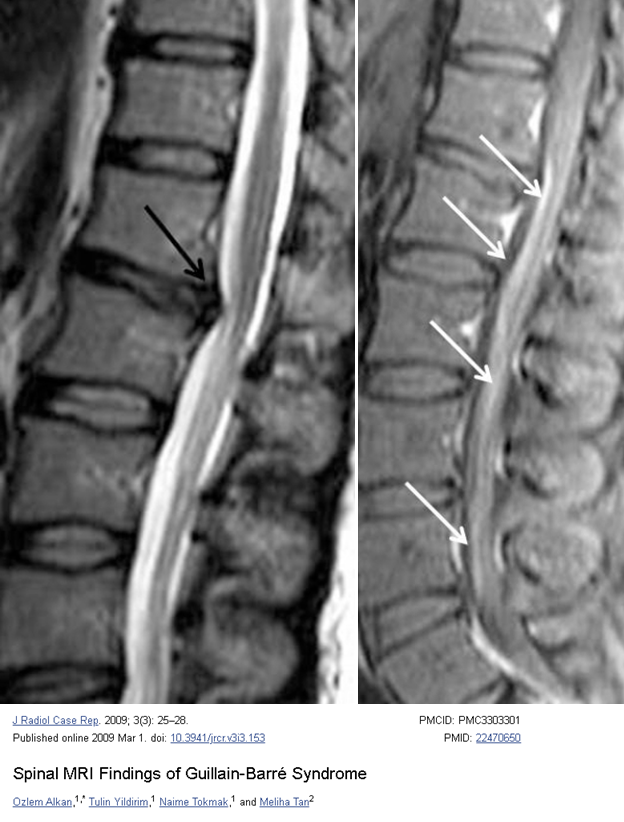

#FOAMrad#NeuroRad#SpineRad: Most viewed Radiology article on https://articl.net from 10/6/19 - 10/12/19 Spinal MRI Findings of Guillain-Barré Syndrome https://www.ncbi.nlm.nih.gov/pmc/articles/PMC3303301/ … For articles on Spine infection imaging visit https://articl.net/resource/spine-infection-imaging … pic.twitter.com/7sYY52gm7f